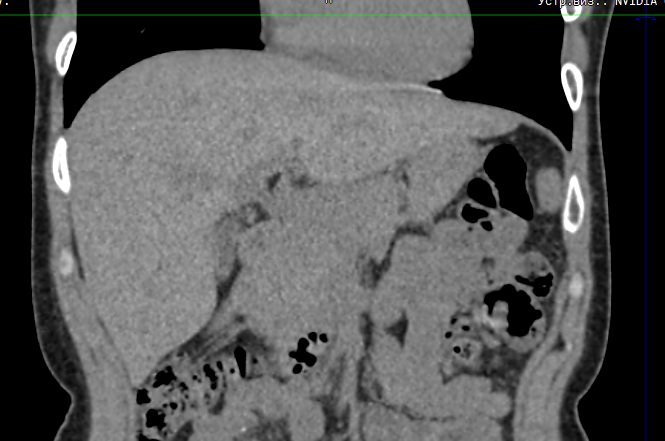

Печеночная ткань имеет обильное кровоснабжение, поэтому часто ультразвуковая диагностика заболеваний печени затруднена. Одним из наиболее информативных методов диагностики является мультиспиральная КТ печени, которая может проводиться в стандартном режиме и с внутривенным болюсным контрастированием. Введение йодсодержащего контрастного вещества значительно повышает диагностическую ценность компьютерной томографии и позволяет, в частности, выявить злокачественное образование на ранней стадии, отличить доброкачественный процесс от злокачественного, визуализировать изменения внутрипеченочных желчных протоков и многие другие патологические процессы.

В нашей клинике сканирование печени выполняется на современном 128-срезовом томографе экспертного класса TOSHIBA AQUILION CXL, который производит послойное сканирование исследуемого органа с последующей цифровой обработкой полученных данных для создания трехмерных изображений печени высокого качества и контрастности. Увеличенное количество детекторов, вмонтированных в аппарат, обеспечивает быстрое время исследования и пониженные дозы рентгеновского излучения, получаемого пациентом.

Мультиспиральная компьютерная томография является быстрым высокоточным и доступным методом исследования, позволяющим обнаружить тяжелые заболевания на ранних стадиях, поставить точный и достоверный диагноз и назначить своевременное лечение.